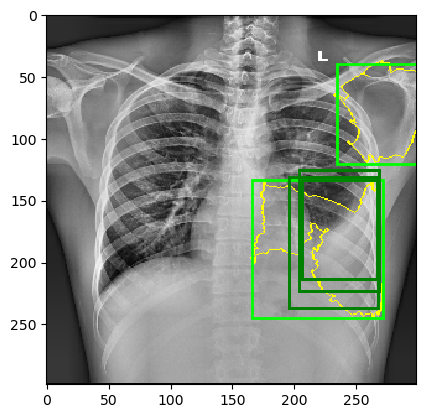

The behavior of MindfulLIME compared to LIME is demonstrated in Figures 4 and 5. Figure 4 showcases random sample 1 with a detected Pleural Effusion condition (annotations highlighted in green), while Figure 5 features random sample 2 with a detected Lung Opacity condition (annotations highlighted in blue). Each figure illustrates the disparities between the ground-truth annotations (darker-colored rectangles) and the generated explanations (lighter-colored rectangles surrounding the yellow border of the selected superpixels). We would like to emphasize that our trained classifier model generalizes well and is not simply memorizing the training data, as evidenced by its performance on a separate evaluation dataset.

The left columns depict the results for the top 1 feature, while the right columns display the results for the top 4 features. The first row presents the output of MindfulLIME, while the second and third rows represent the results of LIME using 1000 and 4000 samples, respectively. When comparing the results of LIME and MindfulLIME for two visual random samples, it becomes evident that MindfulLIME excels in multiple aspects. Firstly, MindfulLIME consistently identifies the top 1 feature with the highest similarity with the actual bounding box. Additionally, as the number of top features increases, MindfulLIME effectively prioritizes and presents more relevant features at the forefront. These findings highlight the enhanced performance and prioritization capabilities of MindfulLIME compared to LIME.